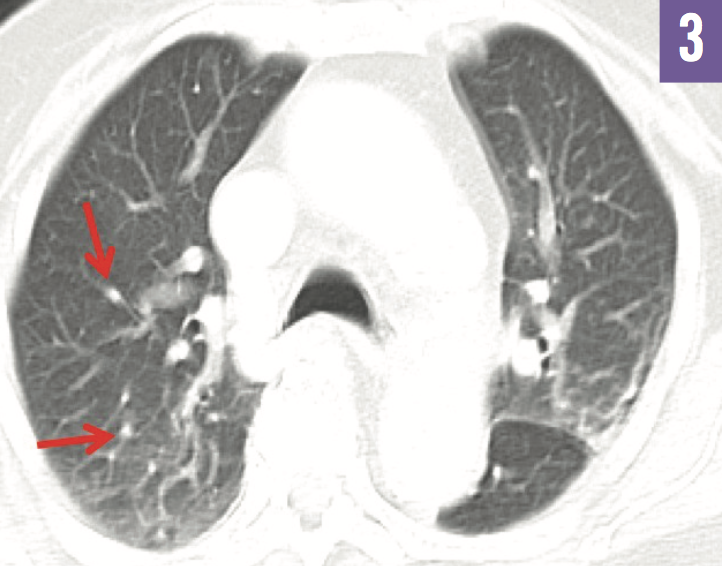

Diagnostic tests. Chest radiograph findings (Figure 1) and results of workups for infectious and hematologic etiologies were unremarkable. Serologic test results were positive for the presence of anti-Saccharomyces cerevisiae antibodies (ASCA), consistent with Crohn disease (CD). Repeat abdominal and pelvic CT scans confirmed the findings of wall thickening and edema of the distal ileum noted on the previous studies (Figure 2), but with a new finding of bilateral ovarian cystic and solid masses concerning for malignancy. Subsequent CT scans of the chest showed disseminated peripheral ground-glass nodules and an indeterminate lung nodule (Figure 3).

FIgure 3: CT of the chest showed ground-glass nodules (arrows).